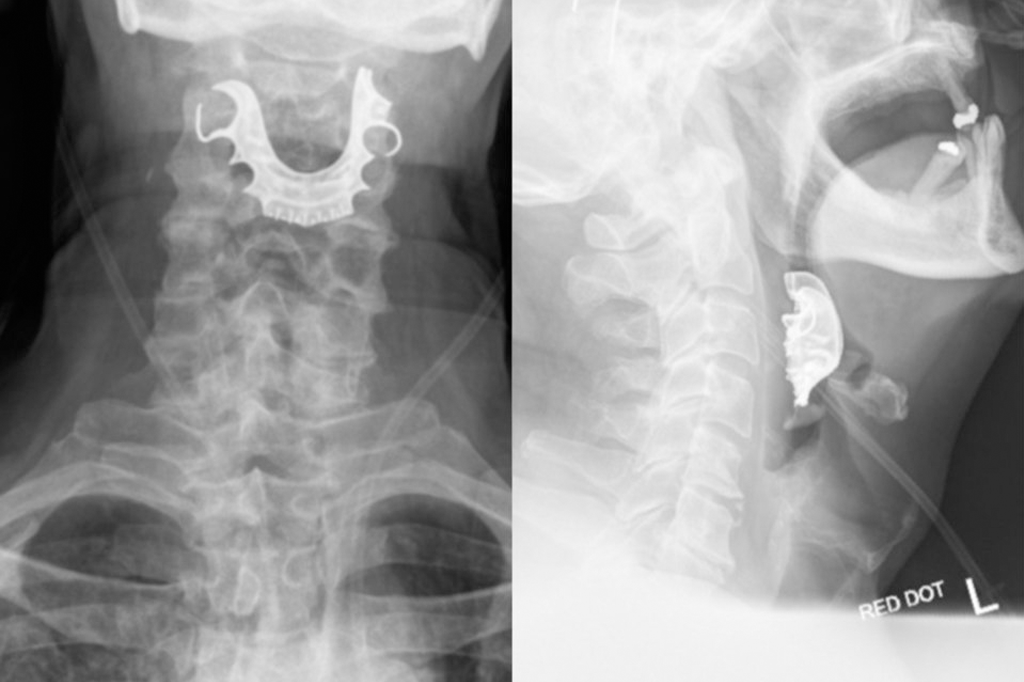

Idoso engoliu sua dentadura durante cirurgia – e ela entalou na garganta

Por Ingrid Luisa 16 ago 2019, 18h36 | Atualizado em 16 ago 2019, 19h05